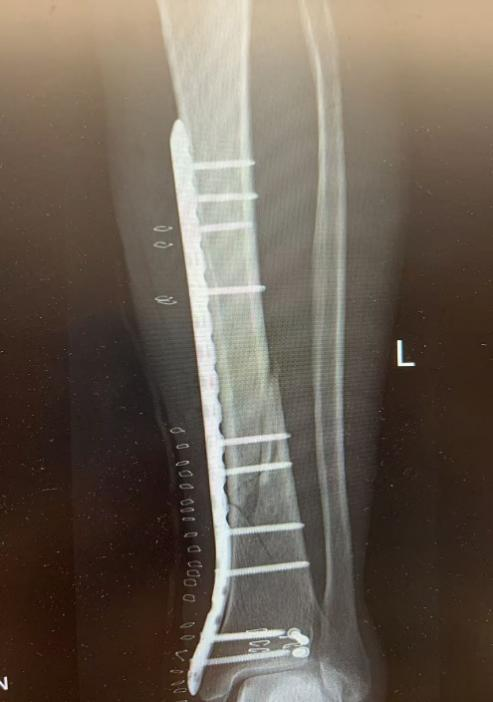

10月4日,59岁张先生不慎被他人电瓶车撞伤致左踝、左小腿疼痛,来院就诊后,王建伟医师团队为患者实行“左胫骨骨折切开复位内固定术”